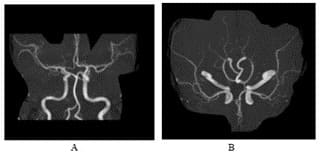

Figure 4: MRA head shows intact vasculature, no evidence of stenoses or obvious dissection.

Figure 5A: 5E-CTA neck done few days later showing intact vasculature.

We present the case of a 30-year-old previously healthy man who presented to the ER on a Sunday morning with acute onset difficulty breathing and weakness in his extremities. He spent most of Friday and Saturday with friends. Earlier that morning he had complained of neck pain and tingling in his hands, which prompted his roommate to bring him to the ER. He was able to walk into the ER, soon after he required assistance to stand up. He now reported, “I can’t move” and “I can’t breathe, I want oxygen”. This was followed by agitation, respiratory distress (Oxygen saturation at 31%) requiring intubation and mechanical ventilation. There was no history of trauma, recent surgical procedures, diabetes, hypertension, heart disease, other significant past medical conditions, and no recent travel history. His vital signs showed normothermia soon followed by hypothermia returning to normothermia (98-degree F; dropping to 94-degree F and 98-degree F over 3 hours), BP 160/98 (then 116/61; followed by 56 mm Hg systolic that improved with fluid boluses. Heart rate was 66/min and later 36/min improving to 80s (36-137 range); EKG showed alternating sinus rhythm and atrial fibrillation with rapid ventricular rate. On day 2 patient failed extubation due to very low tidal volume (80 ml). Chest CT did not show any pathology to explain respiratory failure. His exam revealed quadriplegia and this led to a neurology consultation. Neurological examination showed intact consciousness; he responded to loud verbal and physical stimulation with nods or head shaking. Eye movements initially showed dysconjugate gaze (this resolved in 24 hours), patient exhibited flaccid (0/5) quadriplegia, areflexia and down-going plantar response. He however managed to dislodge the endotracheal tube (ETT) with his tongue movements multiple times. He had normal sensation in his face; below his neck, he had decreased sensation to temperature and pain, but intact light touch and proprioception. Head CT did not show any acute abnormalities. Other investigations on admission revealed normal CBC, CMP; urine drug screen was positive for THC and negative for stimulants, blood EtOH level was < 3. Additional tests included CSF analysis with cell count of 7, normal protein and glucose. CSF culture later came back negative, and he had a normal sed rate (ESR). Brain MRI revealed numerous subcentimeter bilateral cerebellar, posterior temporal and occipital embolic infarcts (Figure 2 A- 2E and Figure 3). Magnetic Resonance Imaging of the cervical spine showed T2 hyperintensity in the territory of the anterior spinal artery extending from C2 to C6 (Figure 1). MRA of the head and neck were normal (Figure 4A and 4B). Transthoracic Echocardiography showed normal ejection fraction, no intracardiac structural abnormalities and no right to left shunt. Transesophageal echocardiography did not reveal any abnormalities in the proximal aorta. CT angiography of head and neck done few days later was normal as well indicating no occlusions or dissections (Figure 5A-5E). He received 1-gram intravenous solumedrol daily for five days based on initial cervical MRI findings in addition to aspirin started after MRI showed acute infarcts. His CSF also showed 14 oligo clonal bands (unclear significance likely secondary to acute ischemia). Hospital course – On day 3 he went into neurogenic shock and multiple episodes of vasovagal bradycardia (HR in the 40s) and demonstrated hemodynamic instability when he was being moved by nursing staff. His exam now showed intact cognition and normal cranial nerve examination. He developed ileus and had frequent episodes of bradycardia (Figure 6), fluctuating blood pressure all part of autonomic dysfunction causing the nurses to panic. He required transvenous pacemaker which was soon replaced with permanent pacemaker. After four weeks his tidal volume improved from 80 ml to 240 ml., he started to regain significant strength in his lower extremities to the point where he was able to stand up and walk up to 25 feet when his vital signs permitted. His upper extremities remained flaccid, areflexic except for his ability to close his hands to gently squeeze a soft ball. Repeat labs including spinal fluid showed similar findings including 14-oligoclonal bands, normal cell count, protein, and glucose. West Nile virus IgM, HTLV-1, HIV, HSV and CSF VDRL testing were all-negative. After eight weeks, his autonomic instability continued to improve and so did his participation in physical therapy sessions. He could now ambulate up to 100 feet using a special walker; however, he remained flaccid in his upper extremities and continued to need intermittent daily ventilator support due to tidal volume at ~300ml. Repeat MRI of his brain and spinal cord was placed on hold due to his pacemaker that requires many weeks for lead maturation.